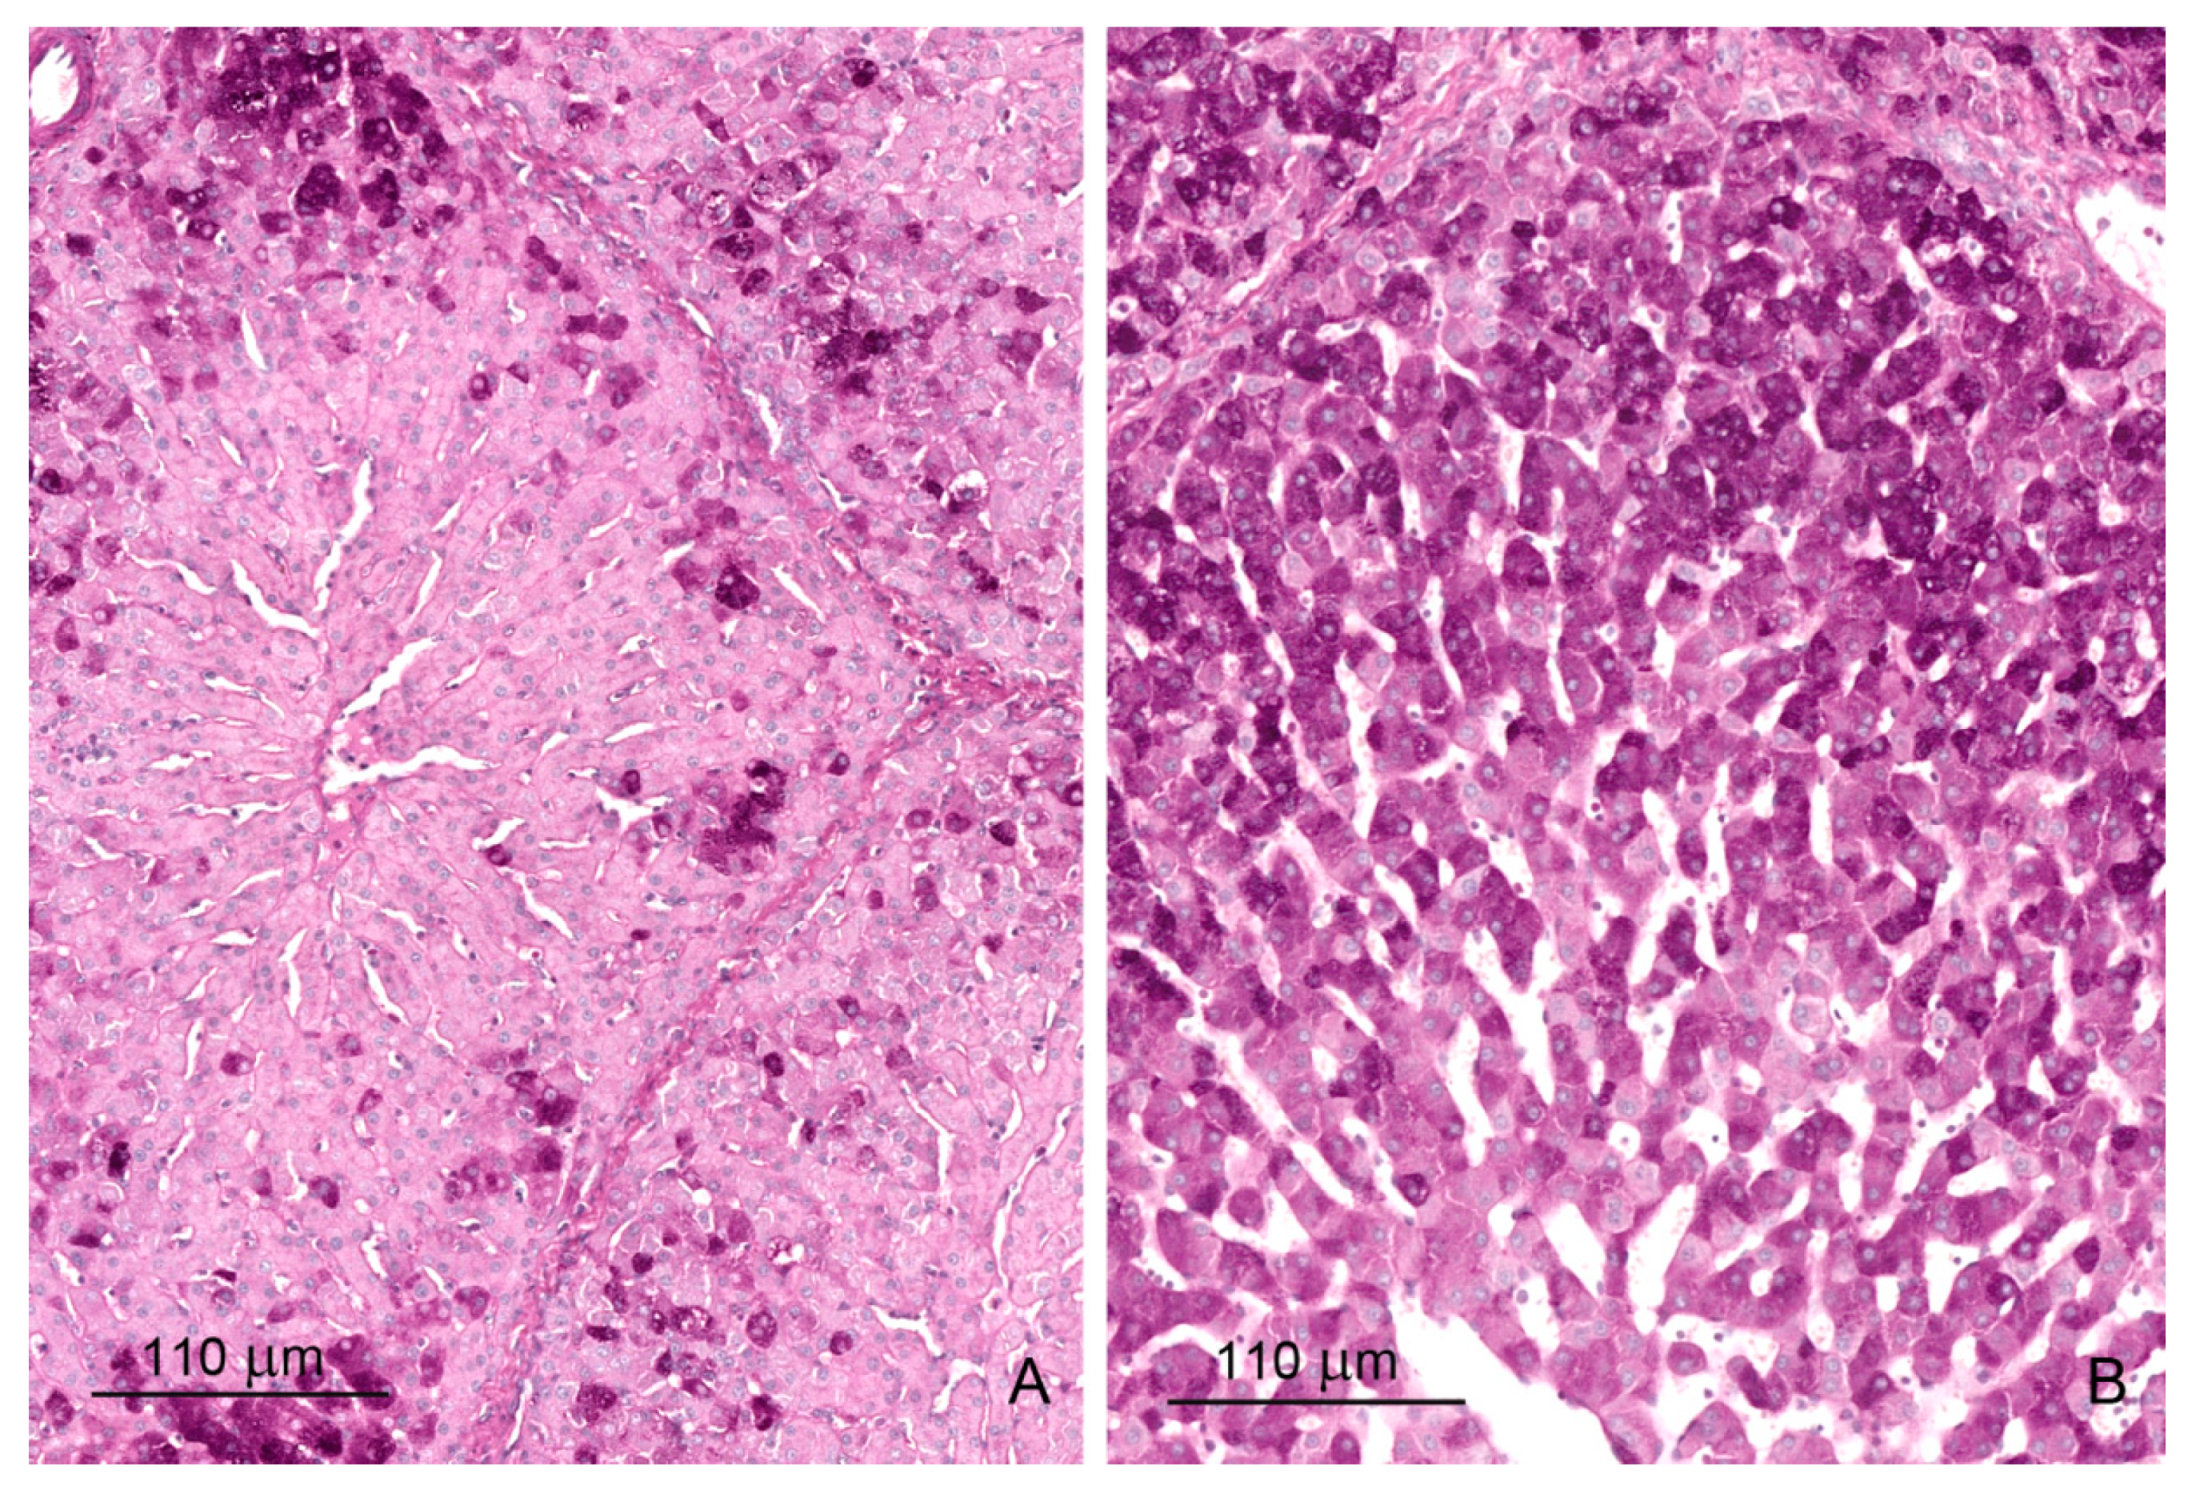

The livers of control pigs had the typical structural characteristic for this species (Figure 1A and Figure 2A). The hepatic lobules were neatly outlined by an envelope of fibrous connective tissue, which interconnected the portal areas. Within each lobule, hepatocytes were arranged in linear cords radiating from the central vein and separated by sinusoids, which had a uniform diameter over their entire length. The limiting plate of hepatocytes bordered the lobule interior from the connective tissue.

Figure 1.

(A,B) Architecture of the liver in a control pig, 6th week of experiment (A) and in a pig receiving deoxynivalenol (DON) for 6 weeks (B). Note the thickening of the interlobular septa. (C) A strip of connective tissue in the liver lobule. A pig was treated with DON for 3 weeks. (D) Focal fibrosis inside the liver lobule of a pig treated with DON for 6 weeks. Note that the central vein is surrounded by connective tissue. Figures (A–D) show hematoxylin and eosin stained sections.

Prominent qualitative differences in the liver architecture were observed between the control group and the DON and DON + ZEN groups. The perilobular connective tissue widened and contained greater amounts of collagen fibers starting from the first week of treatment (Figure 1B and Figure 2B, Table 1). In addition, connective tissue penetrated into the lobule and caused disruption of the limiting plate (Figure 1C). After 6 weeks of treatment, the presence of small scars was pronounced (Figure 1D). The disorganization of hepatic cords was observed in the livers of pigs fed diets contaminated with DON and DON + ZEN for 3 and 6 weeks.